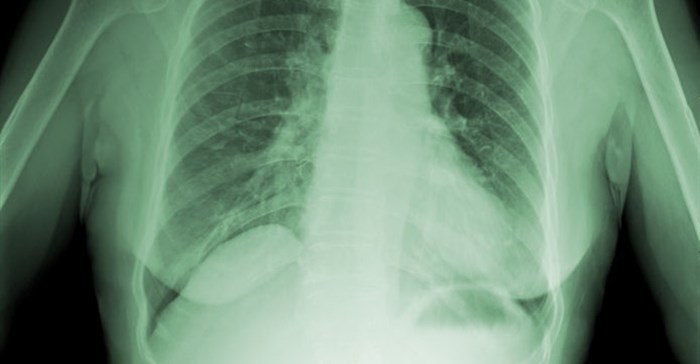

TB screening of inmates has increased to more than 90% on admission with almost 180,000 screened since the programme began in 2014. And almost 32,000 people were screened for TB using chest x-rays in this financial year after exceeding previous targets.